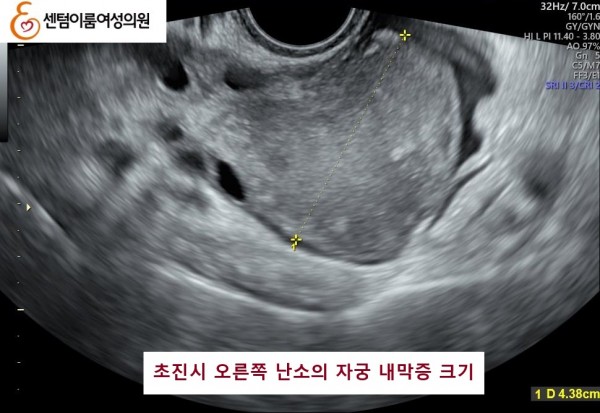

2025.6.28 본원에 내원시 양측 자궁 내막종이오른쪽 4.5cm , 왼쪽 1.3cm 정도 였습니다.

난소의 자궁 내막종은 난소기능 저하를 유발시켜 난자의 갯수를 작게 만듭니다.

본 원에서 수술없이 알콜경화술 3개월 후 양측 다 사라진 사례입니다.